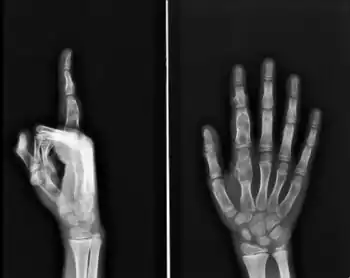

X-ray wrist: Ollier disease in child

X-ray hand:Ollier disease in child